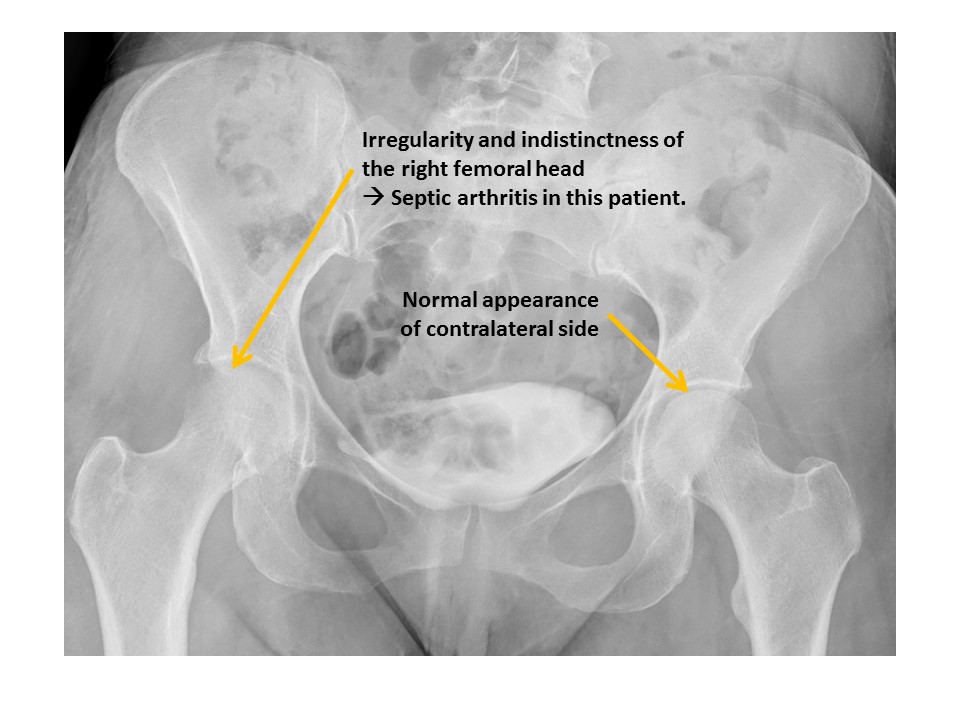

There are radiographic findings of hip osteoarthritis or inflammation. [Yes/No]

The cortices of the femoral heads are irregular. [Yes/No]